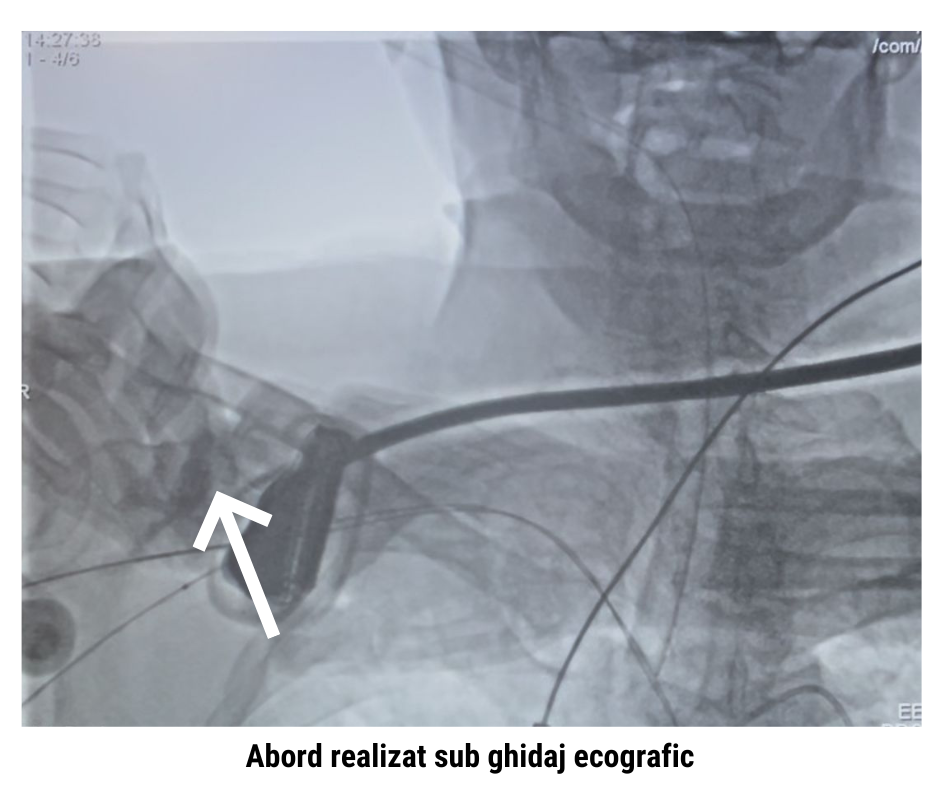

- Incizie controlată la nivel subclavicular drept

- Accesarea arterei subclavii

- Introducerea sistemului de livrare a valvei

- Poziționarea protezei sub ghidaj angiografic și ecocardiografic

- Implantarea valvei cu rezultat hemodinamic optim